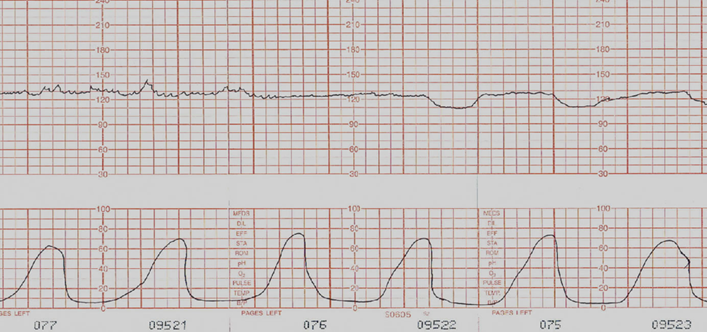

NST, BPP, AFI twice weekly

Continuous FHR monitoring

Watch out for uterine hyperstimulation = FHR!!

Tachysystole more than 6 contraction in 10 min period not enough resting tone for good placental perfusion, maternal exhaustion.

Assessment: RR, DTR, renal fx, FHR, infant RR,

Assessment: racing HR! Fetal arrythmias